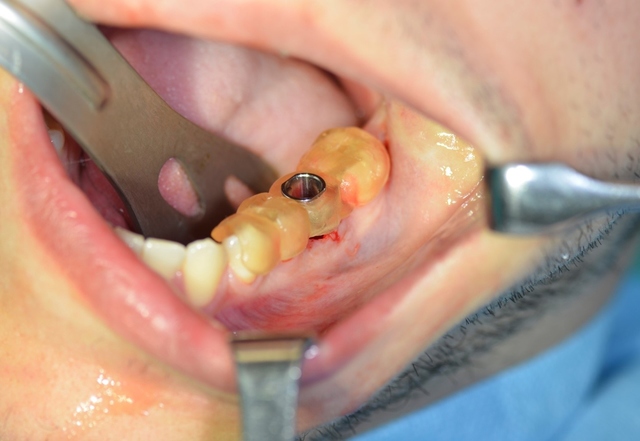

Ryc. 9. Wprowadzony wszczep.

W znieczuleniu miejscowym przeprowadzono minimalnie inwazyjny zabieg usunięcia zęba metodą separacji korzeniowej. Następnie założono szablon implantologiczny i używając systemowej sekwencji wierteł, wypreparowano łoże pod wszczep, który następnie wprowadzono, uzyskując stabilizację pierwotną; zabezpieczono go śrubą zamykającą (Implant Seven, MIS). Wolne przestrzenie zębodołu poekstrakcyjnego wypełniono materiałem kościozastępczym (Bio-Oss, 0,25-1 mm, Geistlich Biomaterials, Szwajcaria), a całość pokryto błoną z osocza bogatopłytkowego oraz lateksowym koferdamem, utrzymywanymi szwami, które pozostawiono na 7 dni (ryc. 7-13).